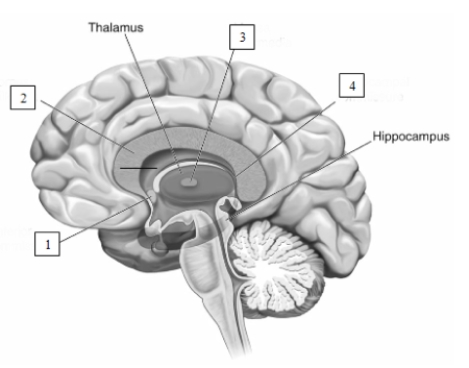

The structure indicated by the number 2 in this illustration is the

The structure indicated by the number 2 in this illustration is the